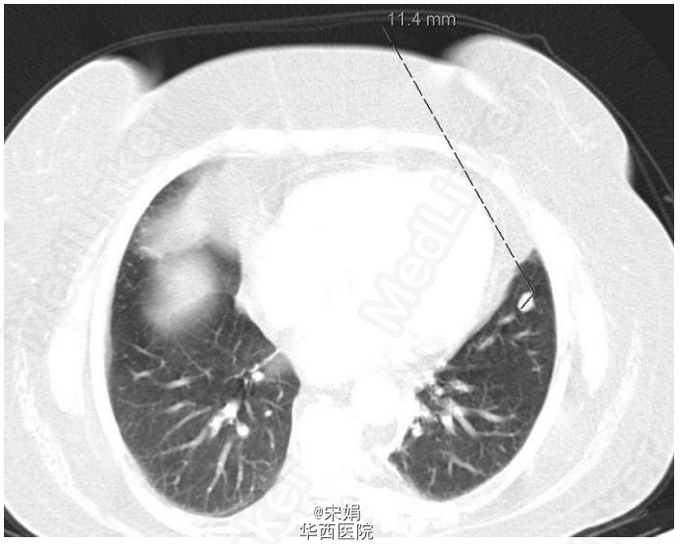

48岁女性,该患者高糖皮质激素表现病史长达 1 年,实验室检查提示为异位 ACTH 所致的 Cushing’s 综合征,各种影像学检查除肺内小结节外无阳性发现,而肺内小结节的功能性检查又无异常发现。最终经过肺叶切除病理证实为肺类癌。